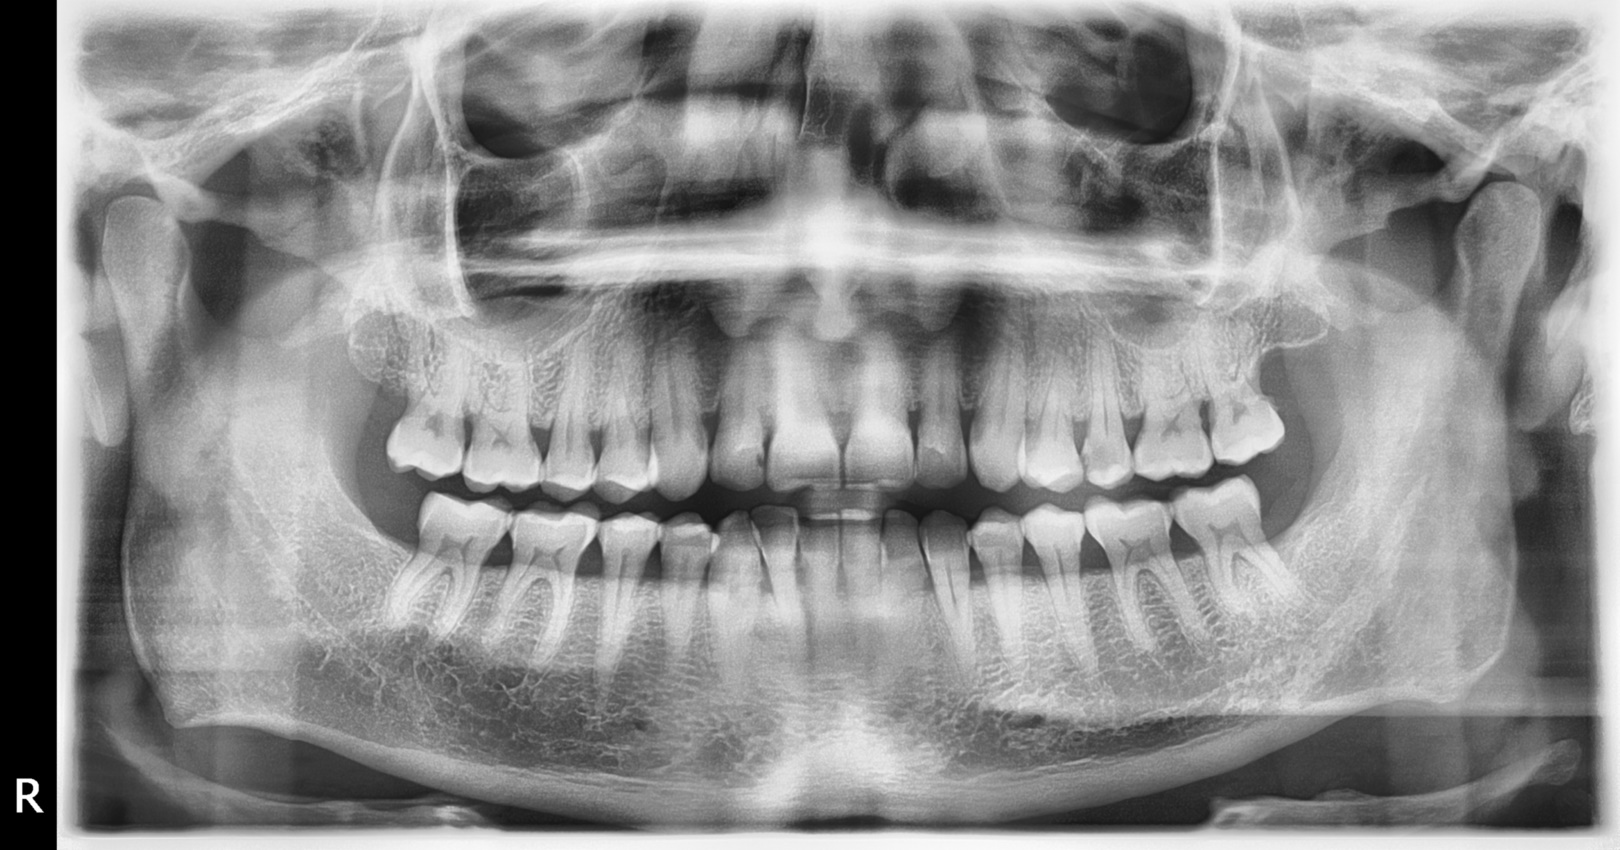

Eine DVT oder CT Aufnahme kommt meistens in der Kieferchirurgie zur Anwendung. In manchen Fällen wird auch bei kieferorthopädischen Behandlungen eine 3D Diagnose benötigt. Vor kieferchirurgischen Eingriffen ist eine vorab 3D Diagnose obligatorisch. Vor einer Implantatoperation müssen auf jeden Fall Voruntersuchungen stattfinden. Zunächst wird einen Panorama Röntgenaufnahme gemacht. Bei der Auswertung der Röntgenaufnahme entscheidet sich, welche Zähen ersetzt werden müssen. Danach muss beurteilt werden, ob genug Knochenmasse vorhanden ist, um überhaupt Implantate zu setzen. Da die Panorama Röntgenaufnahme eine zweidimensionale Aufnahme ist, die nur Höhe und Breite zeigt, muss auch eine 3D Aufnahme mit CT oder Volumentomograph stattfinden, um auch die Knochentiefe zu überprüfen. Desweiteren erlaubt nur eine CT-Aufnahme eine genaue Messung des Knochenangebotes, wovon die Größe der einzusetzenden Implantate abhängt. Neben der Knochenmasse spielt auch der generelle Gesunsheitszustand des Patienten eine entscheidende Rolle ebei der Beurteilung, ob eine entsprechende Behandlung möglich ist. Umstände, die den Erfolg der Implantatinsertion stark beeinflussen, sind z.B. Diabetes oder starkes Rauchen.

Unmittelbar nach der Behandlung wird eine Panorama Röntgenaufnahme gemacht, diese ist für eine gewissenhafte Implantatbehandlung zwingend notwendig. Nach etwa einer Woche werden die Nähte entfernt oder der Kieferchirurg verwendet selbstauflösende Fäden. Die Heilphase dauert in der Regel drei Monate, wenn auch Knochenaufbau oder Sinus-Lift gemacht wurden, kann die Heilungszeit auch sechs, in extremen Fällen bis zu neun Monate dauern. Diese Zeit ist dafür notwendig, damit die Knochenzellen unmittelbar in die Mikroporen auf der Implantatoberfläche hineinwachsen. Dieser Knochenzussammenwuchs (Osseointegration) sorgt für die stabile Befestigung der Zahnimplantate, wonach diese dem späteren, permanenten Kaudruck ohne Beschädigung standhalten können. Danach erfolgt die Anfertigung des Zahnersatzes. Zunächst werden die heilenden Implantate unter dem Gaumen freigesetzt. Das bedeutet keine Operation mehr, sondern nur die Befreiung der sg. Verschlussschraube (Heilschraube) durch einen kleinen Einschnitt an der Schleimhaut und den Einsatz von sg. Gaumenformern (Gingiva-Former), welche in wenigen Tagen den Gaumen formen. Danach erfolgt die Abdrucknahme, worauf basierend der, im Vorfeld geplanter Zahnersatz in dem zahntechnischen Labor in kurzer Zeit erstellt werden kann.

Auch bei komplizierten Zahnentfernungen, vor allem bei der Entfernung von Weisheitszähnen kann eine Zahn CT-Aufnahme notwendig sein, denn nicht selten haben diese Zähne 4 oder 5 Wurzeln, deren Position und Form nicht immer eindeutig basierend auf der 2D Aufnahme festgestellt werden kann.